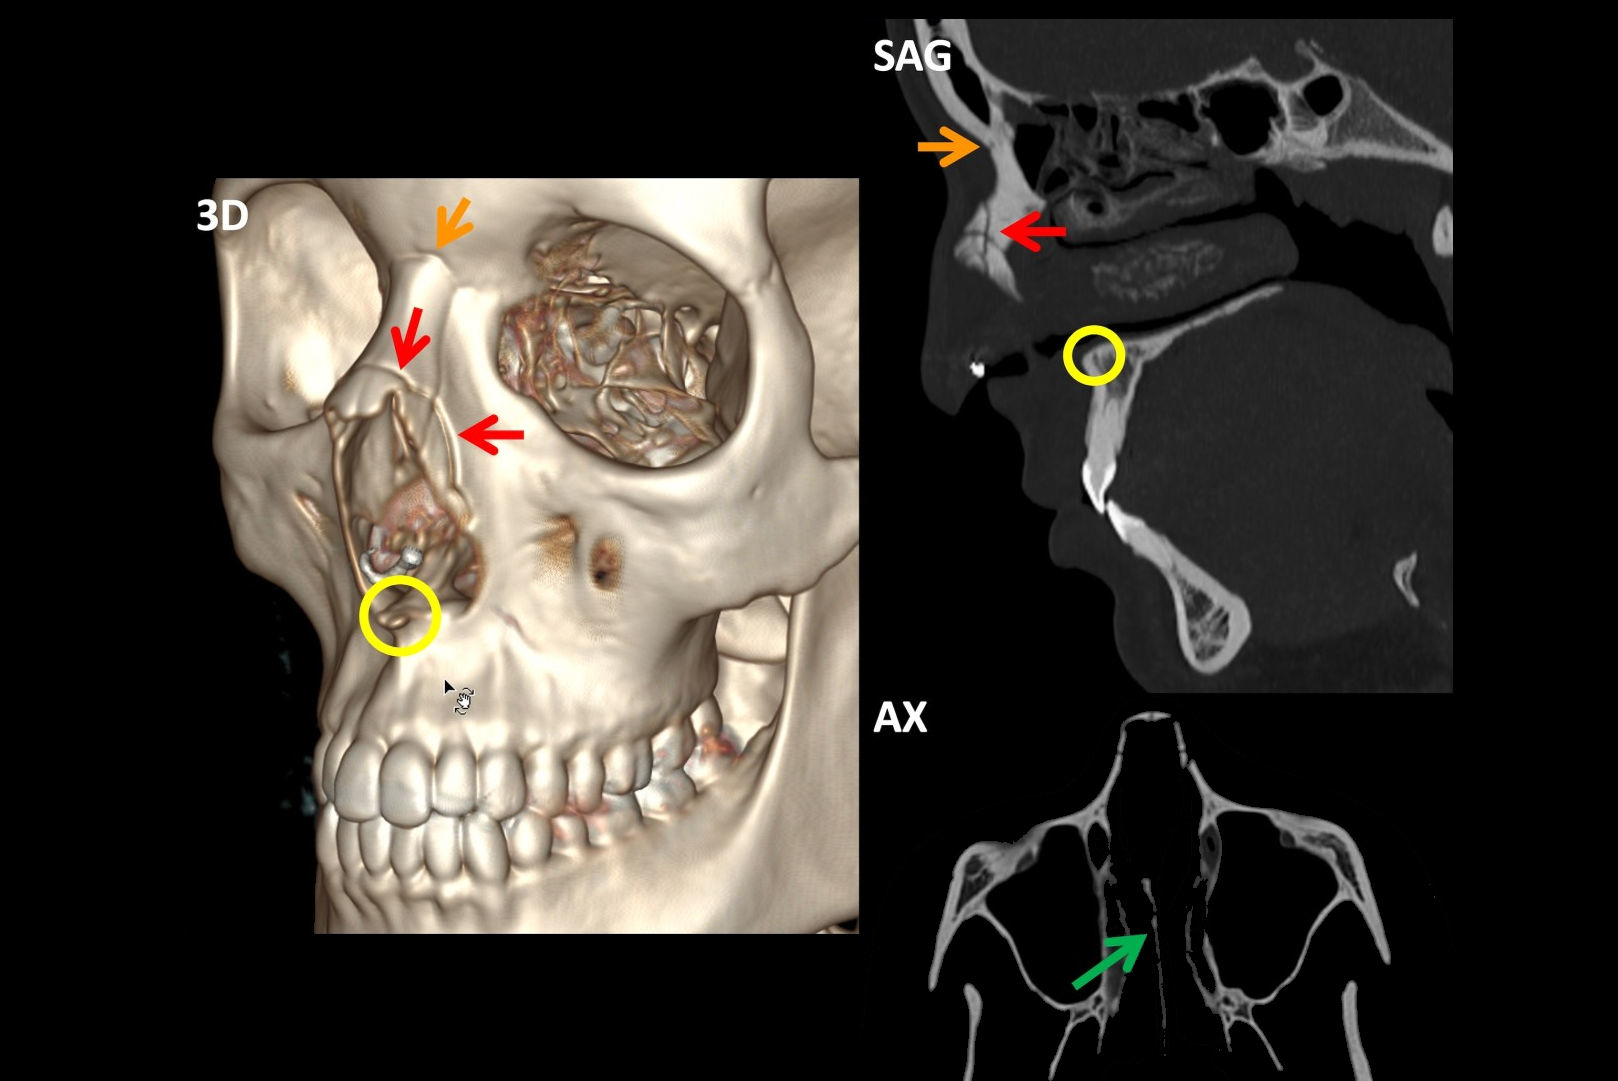

In this example of an incidental finding not being communicated to the patient's GP, a patient in their 30s presented to the emergency department with sudden onset of syncope and associated head injury. After a brain and cervical spine CT, the radiologist documented incidental moderate bilateral internal carotid artery calcification. All figures courtesy of Dr. Chester Yeung et al and presented at RANZCR's 2024 ASM.

Another example of an incidental finding not being communicated to the patient's GP. CT cervical spine coronal reconstruction for a patient in their 50s who presented to the emergency department after syncope with head injury. The radiologist documented incidental emphysematous changes within the lung fields that were captured on a brain and cervical spine CT. This patient was a current smoker who had had no previous investigation, diagnoses, or treatment for chronic obstructive pulmonary disease (COPD).